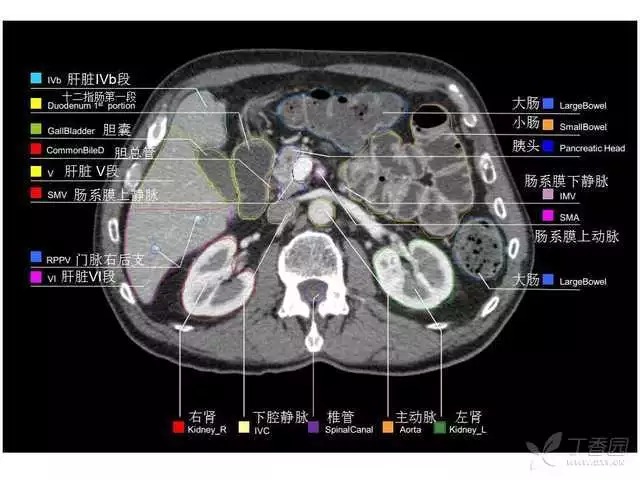

腹部肝脏高清CT断层的图谱

全腹部高清CT图谱,淋巴结彩色图谱,血管解剖图谱大汇总!

超声肝脏分叶及分段

肝脏分段和基本解剖学标志